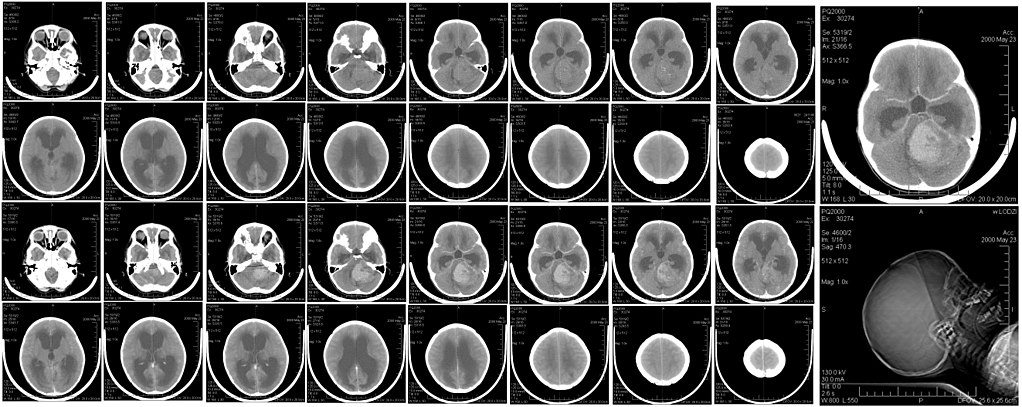

Pilocytic astrocytomas tends to develop in the cerebellum.

Radiology of pilocytic astrocytomas typically show a mural nodule and a cystic lesion are seen on imaging.

Medulloblastomas are a malignant tumor originating from the cerebellum’s granular cells (neuroectoderm).

Medulloblastomas typically occurs in children.

In children, primary central nervous system (CNS) tumors are usually infratentorial.

The three most prevalent central nervous system (CNS) tumors in children are:

- Pilocytic astrocytoma

- Ependymoma

- Medulloblastoma